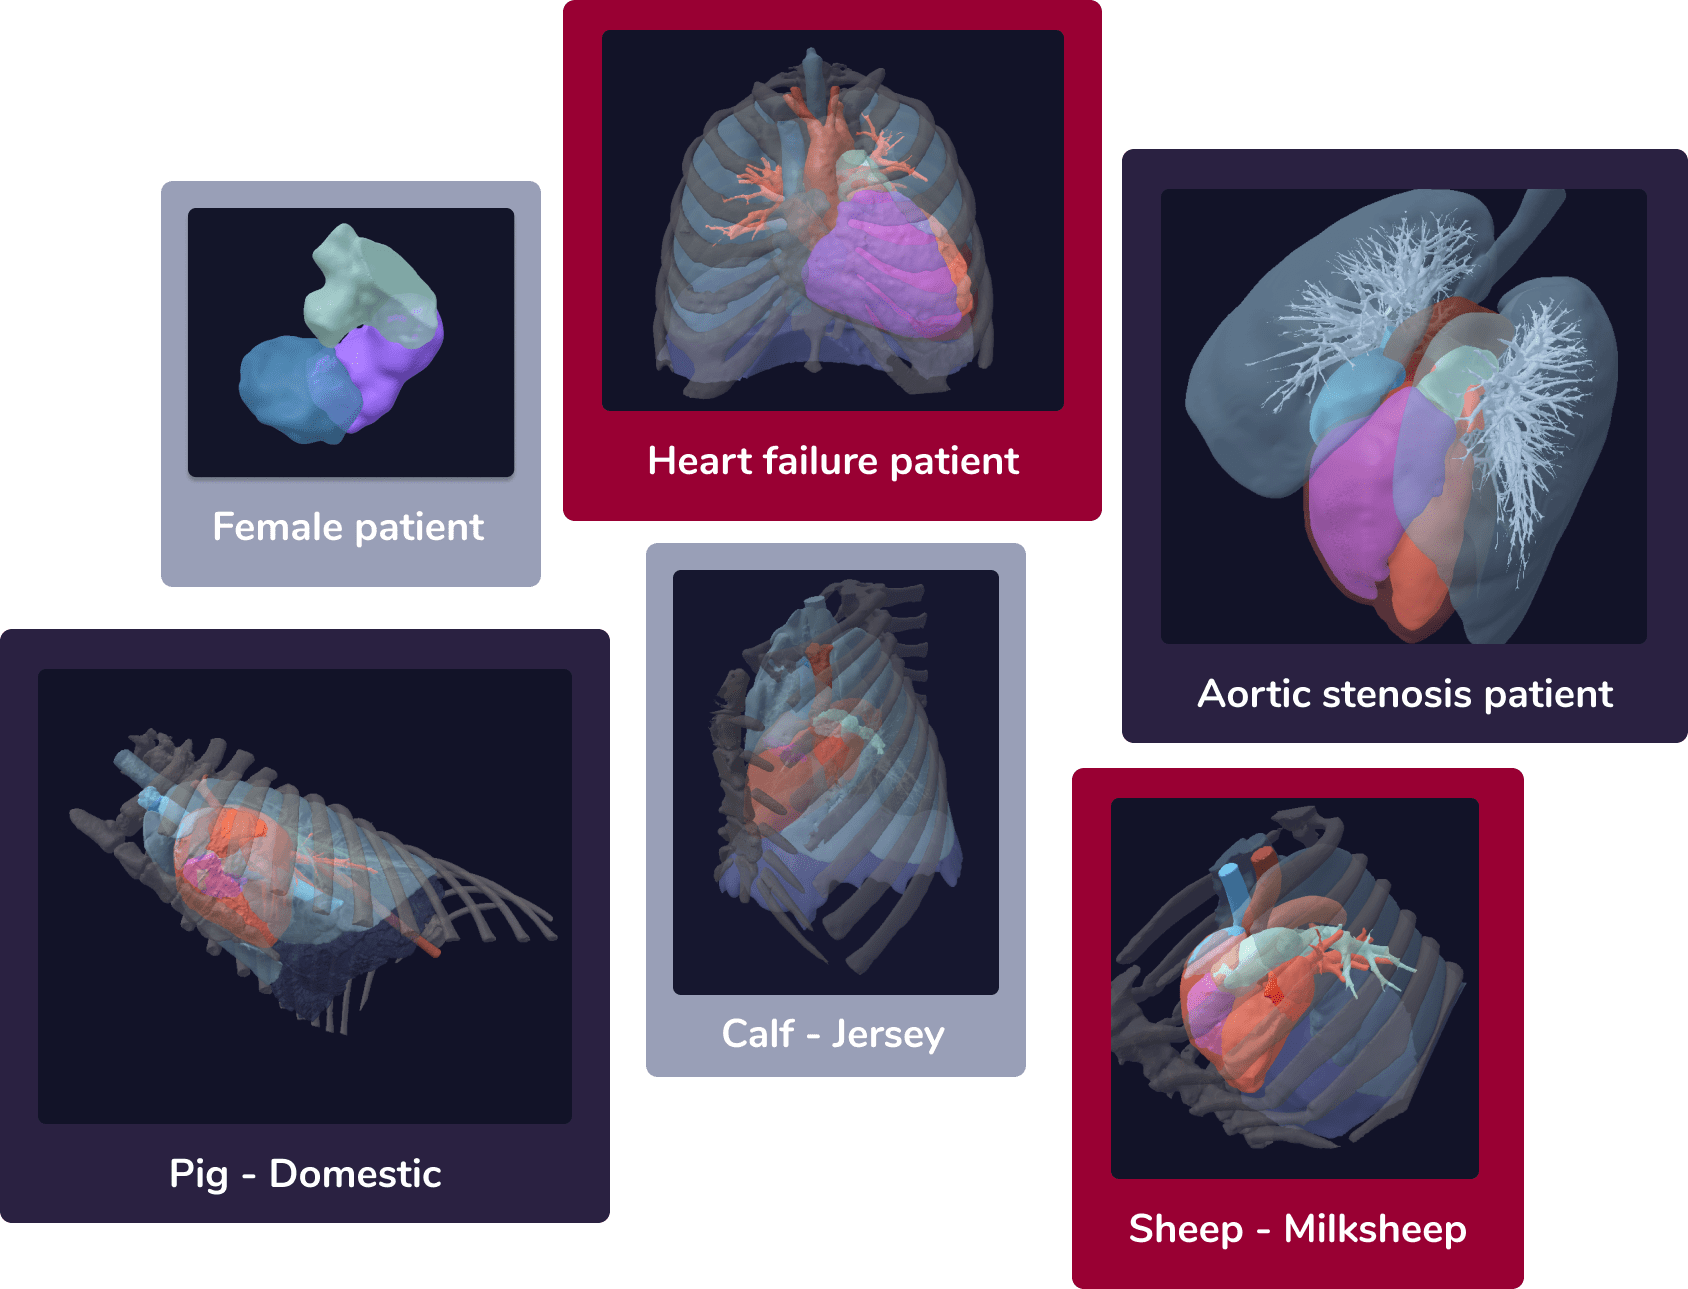

Explore your Target Group

Patient cohort selection01

Create your own virtual patient population that fits to your implant using our extensive database. Detailed criteria allow for a proper selection of the target population.

Validate your Design

Virtual implantation 03

Visualize your device in highly-accurate anatomy models of humans and animals, prior to manufacture.